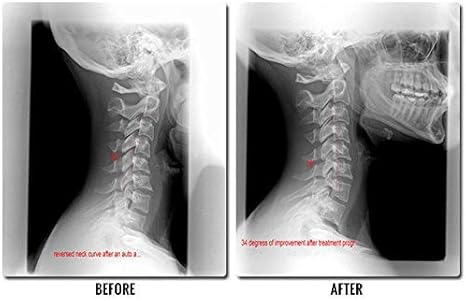

Wenn du die Krümmung des Halses korrigieren musst entferne die Abdeckplatte die über dem Trussrod liegt. Trussrod oder truss rod kommt in der Regel bei Gitarren mit Stahlsaiten zum Einsatz. Sollten Sie diese Krümmung jedoch aufgrund von Verletzungen einer über einen längeren Zeitraum anhaltenden Fehlausrichtung oder aus einem anderen Grund verlieren Möglicherweise ist auch der Rest Ihrer Körperhaltung betroffen.